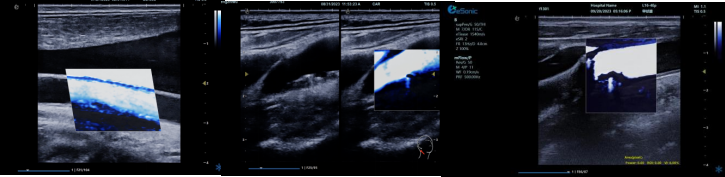

mFlowTM 超微血流显像技术

mFlowTM 超微血流技术在小型机器上率先实现微米级细小血管识别与低速血流捕捉,以往仅高端台式机具备此功能。该技术专注于颈动脉粥样硬化斑块内血流评估,无需造影剂,具有高分辨率、低运动伪像和高帧频成像特点。其优势如下:

image.png

? 运用 3D 壁滤波技术智能分析信号,可探测常规超声难以捕捉的低速血流,灵敏度高。

? 依据 Staub 标准对检查结果分级,直观展示斑块内新生血管血流,为斑块稳定性评估提供新指标。

? 基于多普勒原理,进行频谱测量并可进行VI指数测量,定量评估斑块内新生血管占比。

? 相较超声造影成像,无创便捷,为颈动脉易损斑块评估开辟新途径。

iPlane Vascular 平面波超微细血流显像技术

iPlane Vascular 技术借助 OmniSound?平面波和 3D 壁滤波技术突破,提升超声多普勒分辨率并具备定量测量能力。优势如下:

? 显著提高对低速血流的敏感度,实现高分辨率、高帧频实时微血流成像(分辨率 30 微米、帧频 150 /s),动态显示斑块内新生血管血流。

? 基于多普勒原理进行频谱测量与 VI 指数计算,定量评估斑块内新生血管。

? 成像质量接近造影效果且无需造影剂,无创简便,增强诊断准确性,适用于细微血流变化场景。